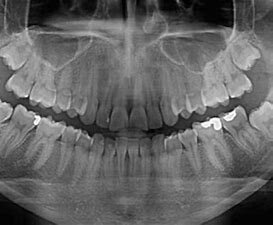

• Descubrimiento de rayos X

Descubrimiento de rayos X

Wilhem Rontgen descubre los rayos X y su capacidad para ver huesos y tejidos duros dentro del cuerpo.

• Rayos x para odontología

Rayos x para odontología

Se crea el primer aparato de rayos X para uso odontológico.